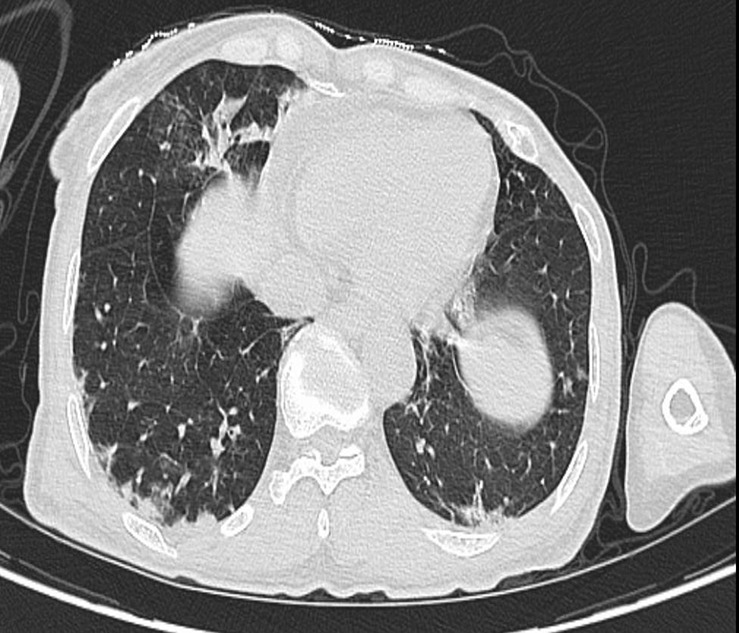

我们报告一个罕见的病例重叠综合征之间的抗mda5阳性皮肌炎(DM)和类风湿关节炎(RA)在65岁的妇女。患者最初诊断为RA,后来出现特征性DM表现,包括特征性DM皮疹、全身无力、食欲不振和体重意外下降。实验室结果显示肌肉酶升高,抗黑色素瘤分化相关基因5 (MDA5)抗体和抗ro52抗体阳性,抗瓜氨酸化蛋白抗体升高。在强的松和霉酚酸酯联合治疗后,患者表现出明显的改善,突出了早期识别和适当处理这种罕见重叠综合征的重要性。

We report a rare case of overlap syndrome between anti-MDA5-positive dermatomyositis (DM) and rheumatoid arthritis (RA) in a 65-year-old woman. Initially diagnosed with RA, the patient later developed characteristic DM manifestations including characteristic DM rash, generalized weakness, poor appetite, and unintentional weight loss. Laboratory findings revealed elevated muscle enzymes, positive anti-melanoma differentiation-associated gene 5 (MDA5) antibody and anti-Ro52 antibodies, and increased anti-citrullinated protein antibodies. The patient showed significant improvement following combination therapy with prednisone and mycophenolate mofetil, highlighting the importance of early recognition and appropriate management of this rare overlap syndrome.